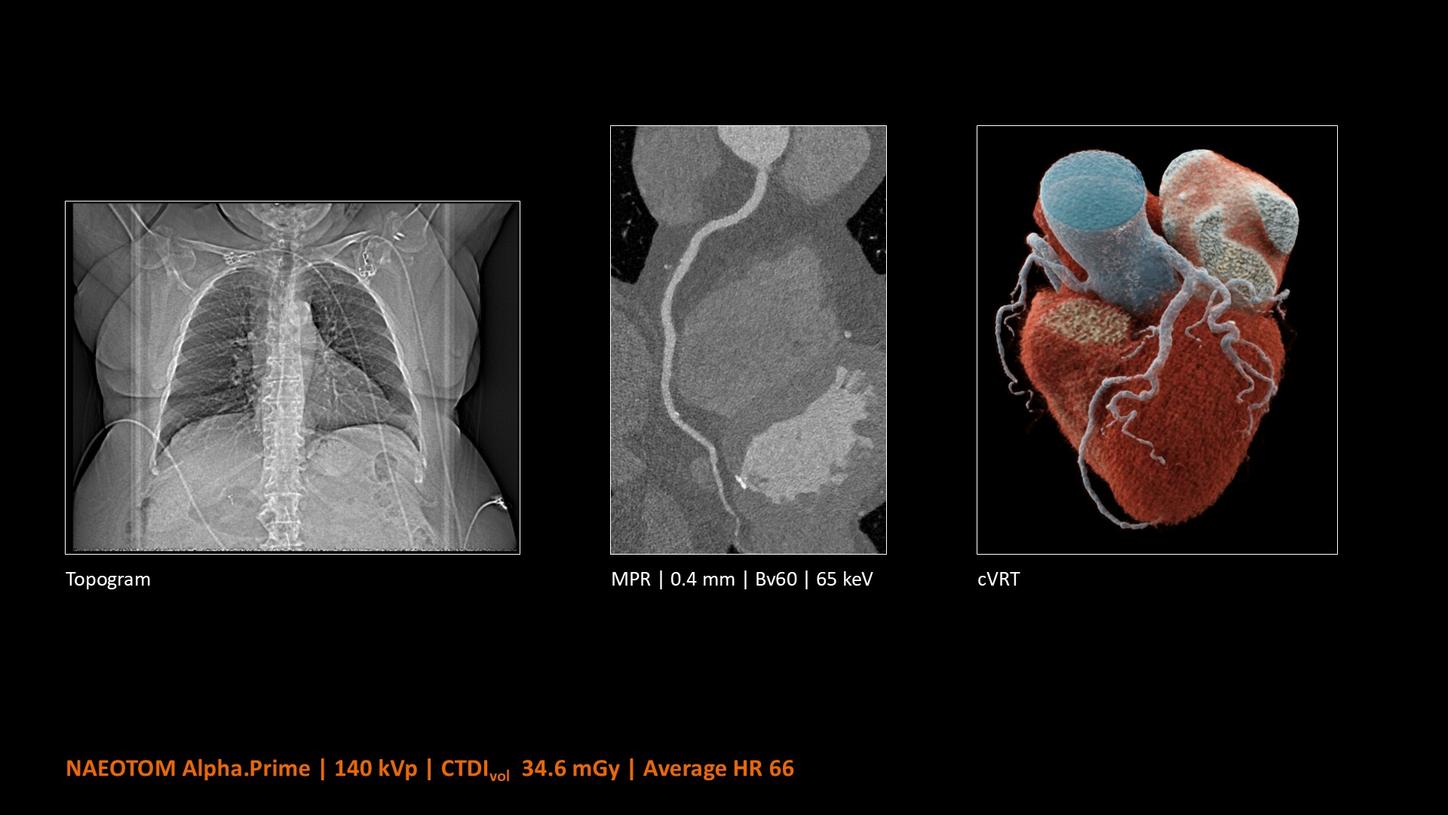

NAEOTOM Alpha® con Quantum Technology®, la nostra nuovissima Dual Source photon-counting CT, offre immagini Quantum HD Cardiac con uno spessore di slice di 0,2 mm. In questo modo è possibile visualizzare dettagli del cuore precedentemente non rilevabili senza incrementi di dose. Inoltre, le informazioni spettrali sono automaticamente disponibili in ogni scansione grazie a un processo di conversione diretta che trasforma i singoli fotoni dei raggi X in un segnale elettrico per creare l'immagine.

Quantum Technology consente una migliore valutazione diagnostica dei vasi coronarici nella TC. Secondo un recente studio, NAEOTOM Alpha e Quantum HD Cardiac potrebbero aver contribuito a ridurre la necessità di un'angiografia coronarica invasiva per il 54% dei pazienti nel rilevamento della malattia coronarica in una popolazione ad alto rischio.¹